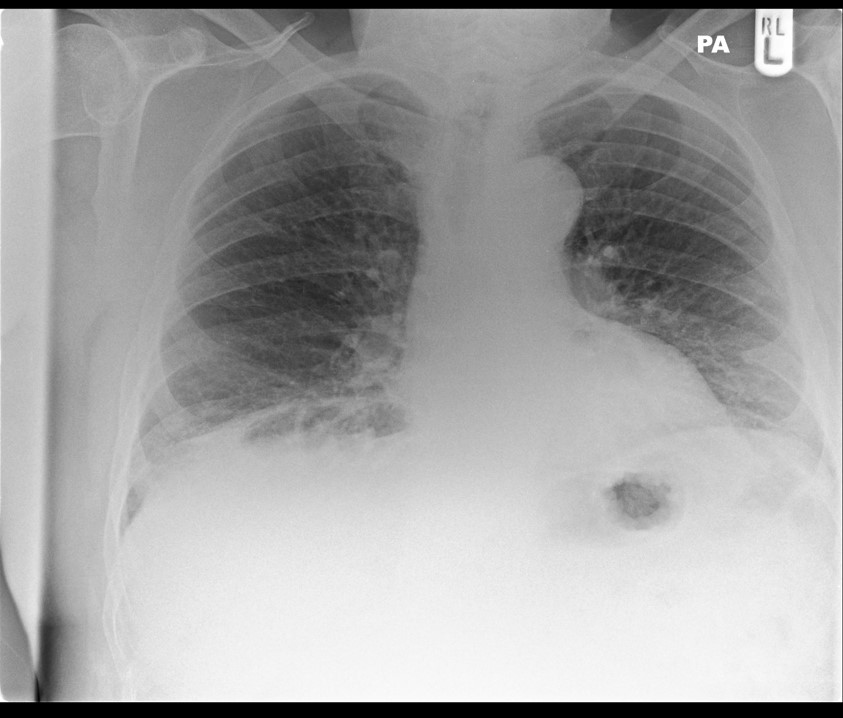

Dull ache on the right side. ?cause

• Right-sided (1)

• Pneumothorax in the apex of the right lung (1)

• The left side is normal (1)